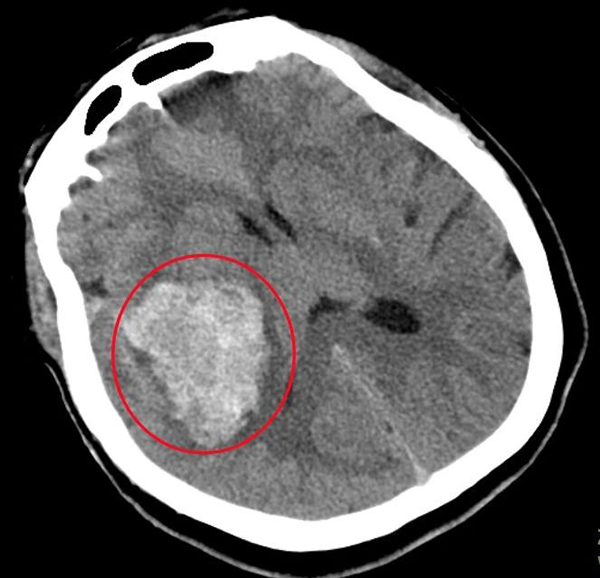

近日,北京市垂杨柳医院急诊抢救室收治了一位被“120”送来的女性患者,患者年仅31岁,突发意识不清伴呕吐胃内容物,有小便失禁。入院时已是深夜,患者深昏迷,双侧瞳孔直径3mm,对光反射消失,血压268/145mmHg,行头部CT提示右侧基底节区脑出血,出血量约64ml,右侧侧脑室明显受压,中线结构移位。患者病情十分危急,急诊科立即联系医院神经外科前来会诊。神经外科医师王绍珍第一时间前往急诊进行会诊。王绍珍详细评估患者病情后,认为患者病情十分危重,遂立即向神经外科主任张锟进行汇报。张锟在得知情况后,也在深夜赶来医院进行会诊,并快速制定了手术方案,积极进行治疗。

▲红圈处为颅内出血区域